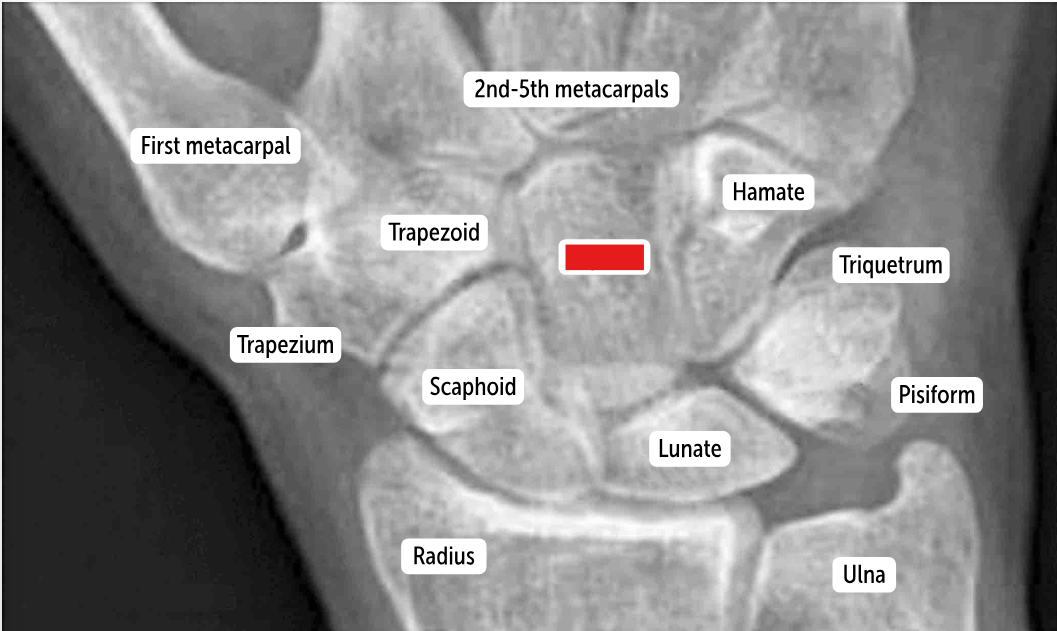

Carpal bones by row:

So Long To Pinky, Here Comes The Thumb

Scaphoid, Lunate, Triquetrum, Pisiform, Hamate, Capitate, Trapezoid, Trapezium

Scaphoid

Lunate

Triquetrum

Pisiform

Hamate

Capitate

Trapezoid

Trapezium